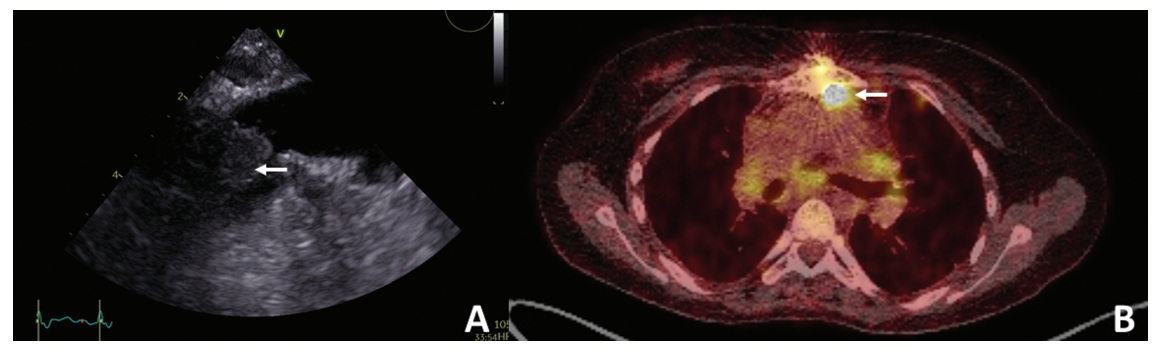

患者入院时发热高达39°C、呕吐,间歇性咳嗽。曾在外院行4次心脏手术及多次导管介入治疗。这些包括法洛四联症矫正术,右心室流出道(RVOT)导管重复扩张,因严重肺功能不全在RVOT植入 Contegra移植物,因Contegra心内膜炎(金黄色葡萄球菌)植入肺部同种移植物,念珠菌引起的胸骨伤口感染,真空辅助封闭(VAC)治疗以及胸骨重新连接与无泵心包缺损封闭过程中的同种移植损伤。术前经食管超声心动图显示,靠近肺动脉分叉处低密度结构(横径约 14mm),符合血栓或赘生物(图1A),引起梗阻(Vmax> 4m/s)。正电子发射断层扫描/计算机断层扫描(PET-CT)显示同种移植物区域的病理示踪剂摄取(图1B)。

图1. (A)经食管超声心动图显示肺动脉分叉附近低密度结构,横径约 14mm,符合血栓或赘生物(箭头)。(B)氟脱氧葡萄糖正电子发射断层扫描/计算机断层扫描(FDG-PET-CT)显示附着胸骨的右心室流出道(RVOT)高活性(箭头)。